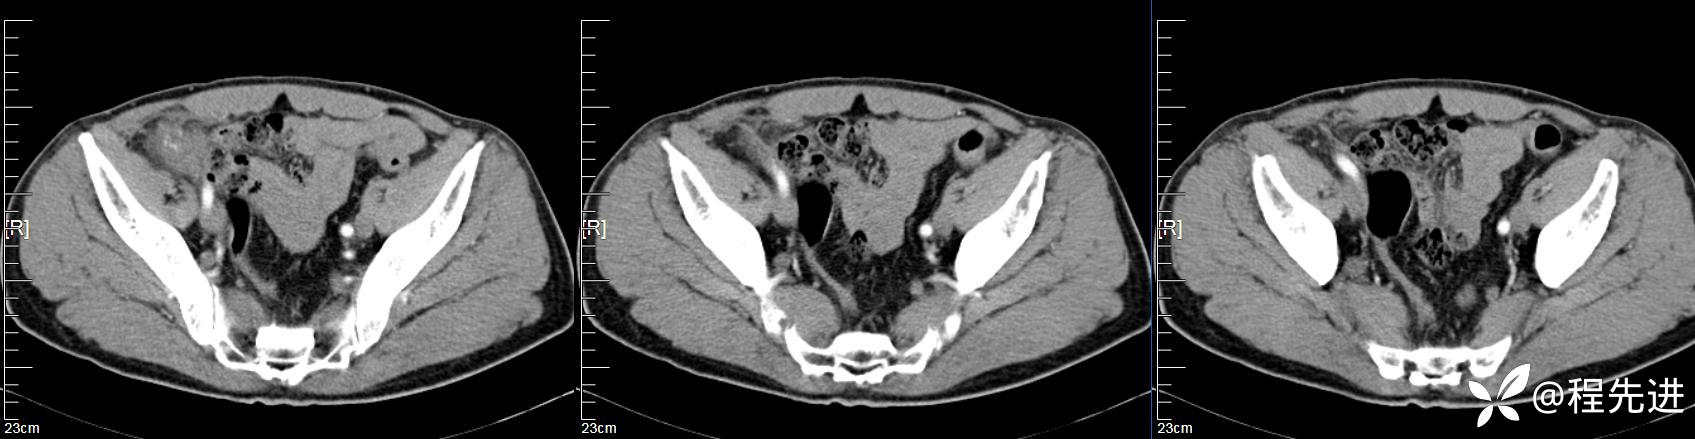

【患者信息】:男,61岁

【现病史及既往史】:右下腹部疼痛伴腹胀2天

【影像检查】